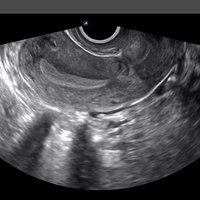

Für das X-CUBE i9 steht ein umfangreiches Schallkopfportfolio zur Verfügung. Somit kann das komplette internistische Spektrum inklusive der Kardiologie, aber auch Untersuchungen des Bewegungsapparates mit hochauflösenden Schallköpfen bis 25 MHz oder gynäkologische bzw. urologische Untersuchungen mit der Qualität eines Standsystems durchgeführt werden.

Dabei kommen die aus der X-CUBE Reihe bekannten Einkristall-Schallköpfe der neuesten Generation und nahtlose Schallköpfe zum Einsatz.

• EV3-10T (3-10 MHz) für Ultraschalluntersuchungen in Bereichen Geburtshilfe Gynäkologie, fetales Echo, Urologie, EM

• EC3-10T (3-10 MHz) für Ultraschalluntersuchungen in Bereichen Geburtshilfe, Gynäkologie, fetales Echo, Urologie, EM